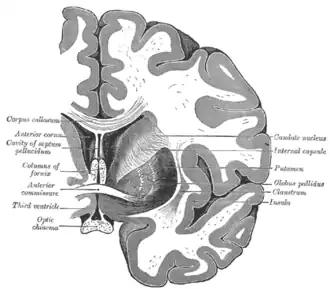

Anatomie

Samen met het putamen vormt de nucleus caudatus het striatum dorsale, dat functioneel als één structuur wordt gezien. Anatomisch gezien worden de twee gescheiden door een belangrijke baan van witte stof: de capsula interna. De nucleus caudatus bevindt zich in beide hersenhelften, aan de wand van de zijventrikels en schrijlings op de thalamus.[7] De boogvormige kern heeft een dikke kop en loopt steeds dunner uit in een soort staart, waaraan de structuur haar naam te danken heeft.